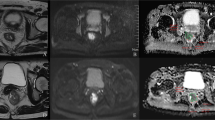

This study explored models of monoexponential diffusion-weighted imaging (DWI), diffusion kurtosis imaging (DKI), stretched exponential (SEM), fractional-order calculus (FROC), and continuous-time random-walk (CTRW) as diagnostic tools for assessing pathological prognostic factors in patients with resectable rectal cancer (RRC).

RRC patients who underwent radical surgery were included. The apparent diffusion coefficient (ADC), the mean kurtosis (MK) and mean diffusion (MD) from the DKI model, the distributed diffusion coefficient (DDC) and α from the SEM model, D, β and u from the FROC model, and D, α and β from the CTRW model were assessed.

There were a total of 181 patients. The area under the receiver operating characteristic (ROC) curve (AUC) of CTRW-α for predicting histology type was significantly higher than that of FROC-u (0.780 vs. 0.671, p = 0.043). The AUC of CTRW-α for predicting pT stage was significantly higher than that of FROC-u and ADC (0.786 vs.0.683, p = 0.043; 0.786 vs. 0.682, p = 0.030), the difference in predictive efficacy of FROC-u between ADC and MK was not statistically significant [0.683 vs. 0.682, p = 0.981; 0.683 vs. 0.703, p = 0.720]; the difference between the predictive efficacy of MK and ADC was not statistically significant (p = 0.696). The AUC of CTRW (α + β) (0.781) was significantly higher than that of FROC-u (0.781 vs. 0.625, p = 0.003) in predicting pN stage but not significantly different from that of MK (p = 0.108).

The CTRW and DKI models may serve as imaging biomarkers to predict pathological prognostic factors in RRC patients before surgery.